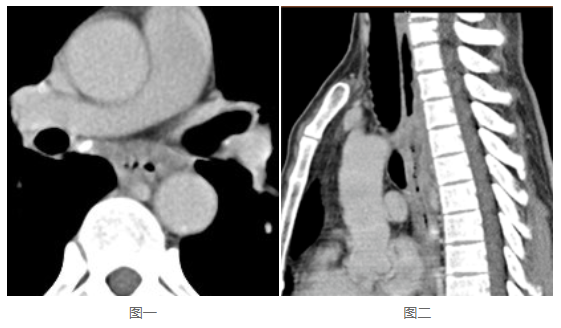

几乎所有PACS软件都具备缩放、平移、调窗、测量、电影功能,这部分功能适用于平片、DSA等;也具备分窗、MPR、MIP、VR功能,适用于CT、MR。因此PACS工作站适用于绝大部分影像的后处理,是阅片写报告的基本要求。那么,这些功能在移动端,采用B/S方式使用时,是不是仍然具备?是不是还适用于绝大部分类型的影像?如果是,那么可以认为具备阅片写报告的功能要求;如果不是,显然,对于部分类型的影像,阅片写报告则相对困难,甚至可能无法判断。看下这两张图:

这是同一病灶的不同视角,图一是横断位,图二是矢状位。很明显,图二对于食管的侵蚀显示得更为直观。这应该就是《浙江省数字影像服务专家共识》明确要求“保存检查时生成的各种成像体位的完整序列影像”的原因。那么,如果PACS在存储影像时仅仅存储了横断位,就一定需要影像软件本身能将矢状位影像重建出来。